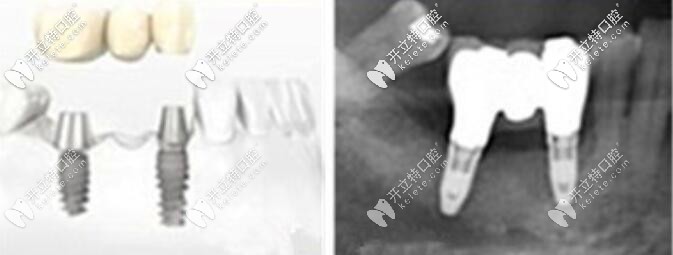

這是一個(gè)缺三種2的案例圖↓↓↓

這是一個(gè)缺三顆牙種2顆植體的案例圖